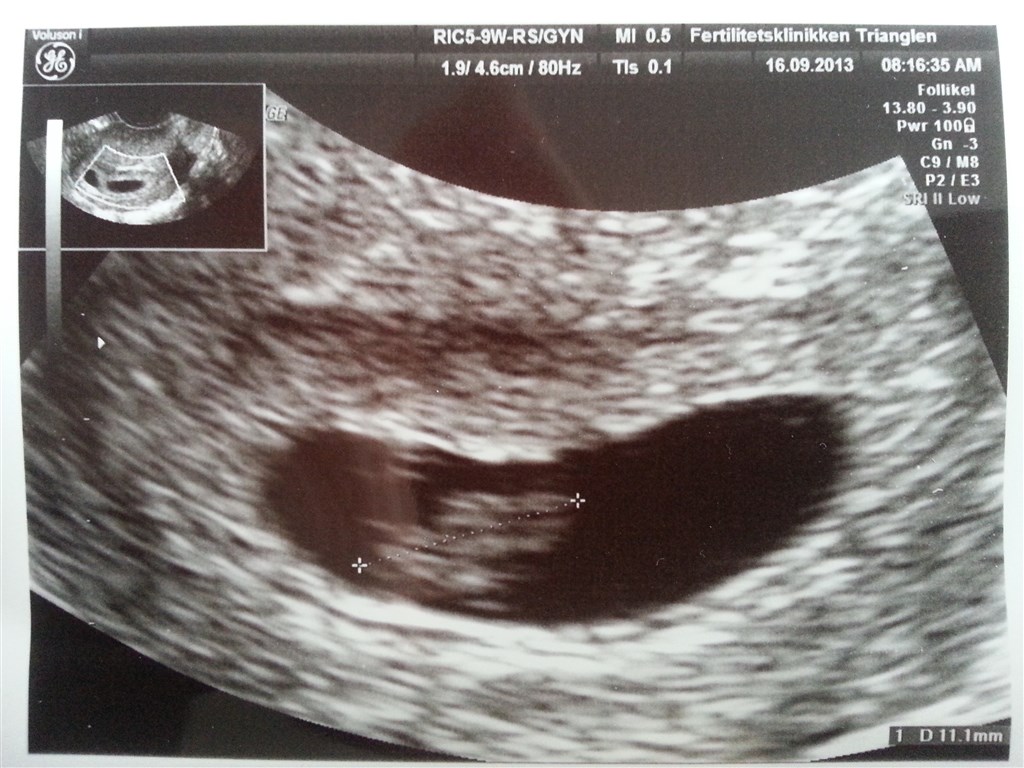

Ja, det må godt nok have været syret at se! Og vildt at se hjerteblink.

Men der har så måske været et ekstra foster, siden der var en ekstra blommesæk? - synes forresten at det er rigtig fint at du så skal til scanning igen. Det bliver dejligt at få lov til at se den lille igen.

Ja, der er højst sandsynligt et ekstra foster, som har sat sig fast men ikke udviklet sig videre. Der var ikke noget at se inde i blommesækken. Jeg håber at den er forsvundet til kontrolscanningen, og alt er som det skal være